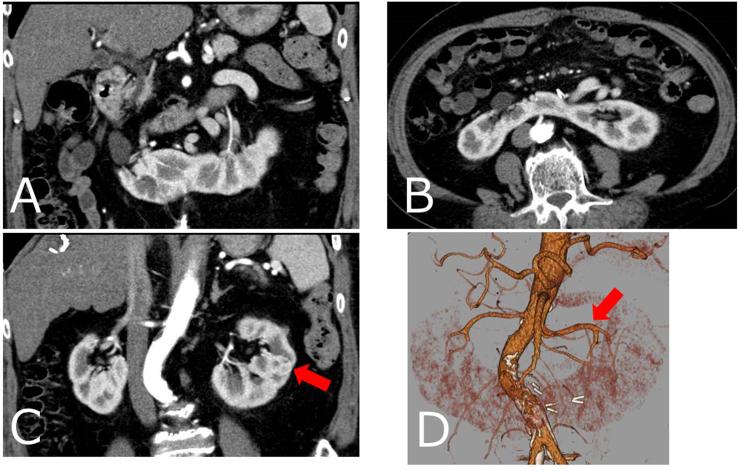

Horseshoe kidney is one of the most common congenital renal fusion anomalies and the incidence of renal cell carcinoma in horseshoe kidney is predicted to be approximately 5.2/100000 individuals. Because horseshoe kidney merges malformations and vascular changes, open surgery is the standard for treatment. There are no reports of robot-assisted partial nephrectomy (RAPN) for renal cell carcinoma in horseshoe kidney. We describe for the first time the safety and the utility of RAPN in a horseshoe kidney with renal cell carcinoma.